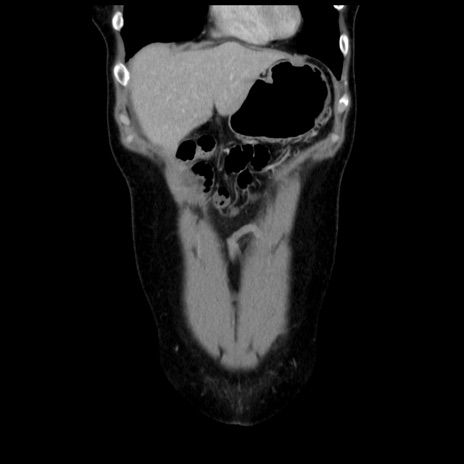

症例10(冠状断像)

【症例】 50歳代女性

【主訴】 腹痛

【現病歴】前日生レバーを食べた。今朝に排便あり。 昼前に突然発症の腹痛を生じ、当院救急外来を受診した。

【既往歴】 子宮筋腫にてで子宮全摘後

【身体所見】 意識清明、腹部:平坦、軟、下腹部やや左を中心に圧痛・反跳痛あり、筋性防御あり

【データ】WBC 7800、CRP 0.07